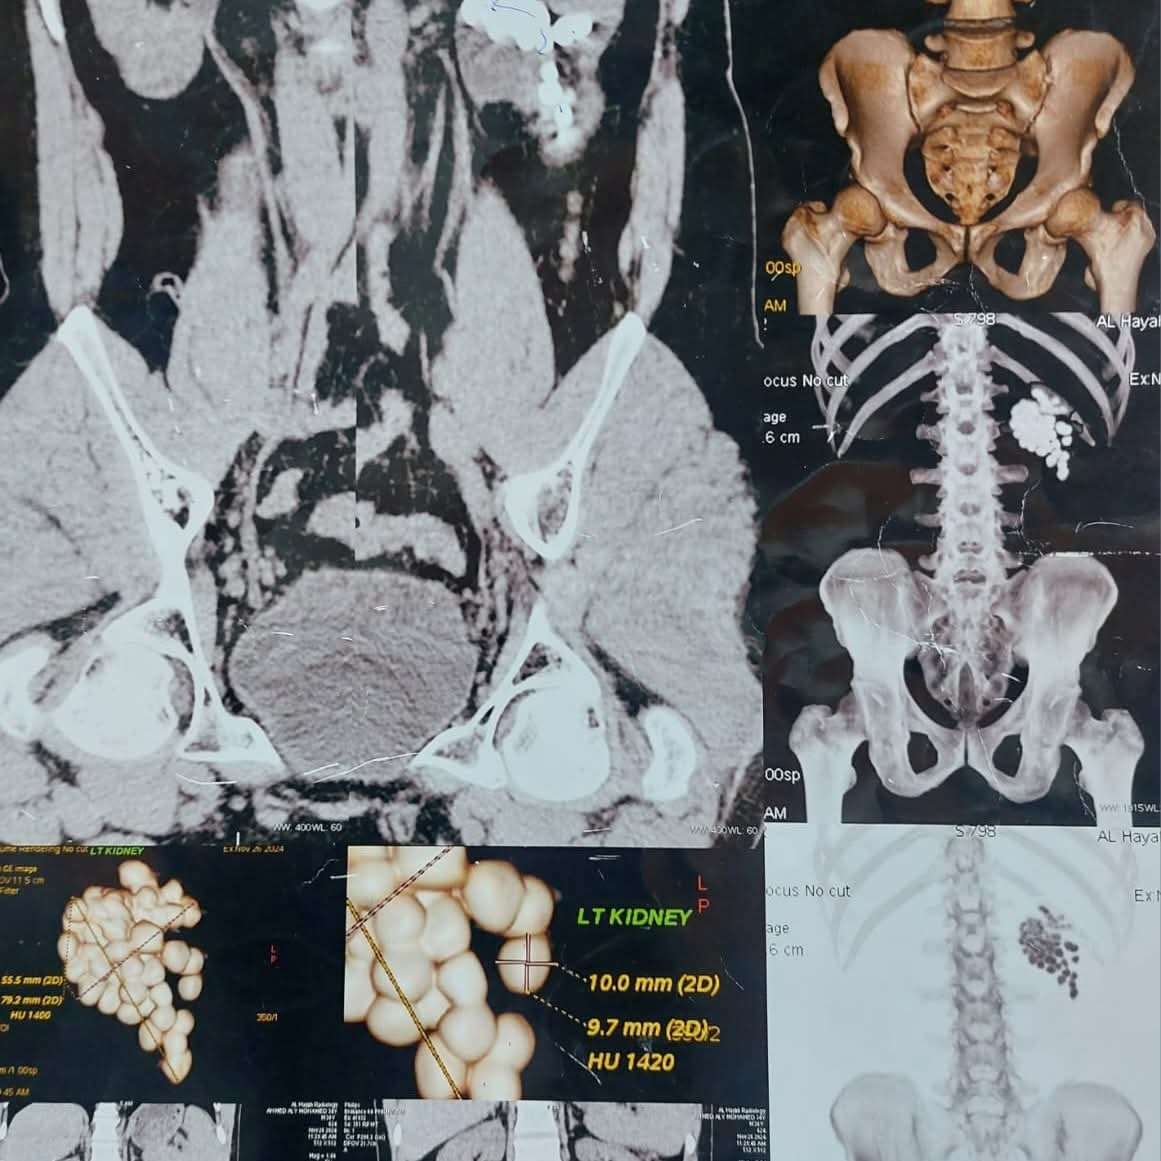

عملية استغرقت ساعتين.. استخراج 58 حصوة من كلية مريض بمستشفى قنا الجامعي

أعلنت مستشفيات قنا الجامعية، نجاح فريق طبي متخصص بمستشفى المعبر الجامعي، في إجراء عملية دقيقة لاستخراج 58 حصوة من الكلية اليسرى لمريض يبلغ من العمر 40 عامًا، وذلك باستخدام أحدث تقنيات مناظير الكلى المتقدمة.

وأوضح الأستاذ الدكتور مصطفى عبد الرازق رئيس قسم المسالك البولية، أن المريض وصل وهو يعاني من آلام متكررة وارتفاع في نسبة الأملاح، وبفحصه تبيّن وجود عدد كبير من الحصوات المتجمعة في حوض الكلية اليسرى، ما استدعى التدخل الجراحي حفاظًا على وظائف الكلية.

وأشار إلى أنه تم تجهيز المريض وإخضاعه للتخدير العام، ثم البدء في العملية من خلال فتحة صغيرة لا تتجاوز سنتيمترًا واحدًا للوصول إلى الكلية، قبل تفتيت الحصوات باستخدام تقنيات التفتيت الهوائي والليزر تبعًا لطبيعة كل حصوة.

واستمرت العملية نحو ساعتين، تمكن خلالها الفريق الطبي من إزالة جميع الحصوات والتأكد من تنظيف حوض الكلية بالكامل، مع تركيب أنبوب تصريف مؤقت لضمان خروج السوائل بصورة آمنة.